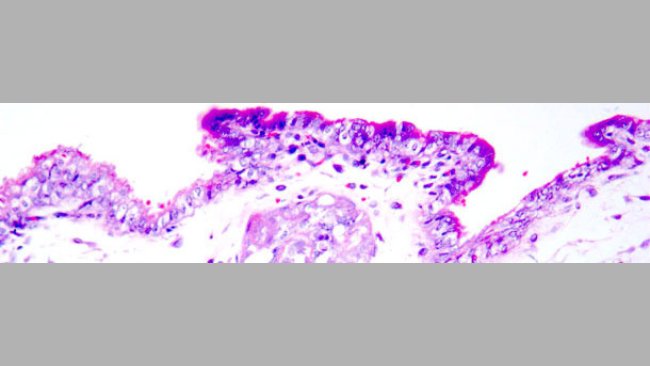

Transmisión placentaria del circovirus porcino tipo 2